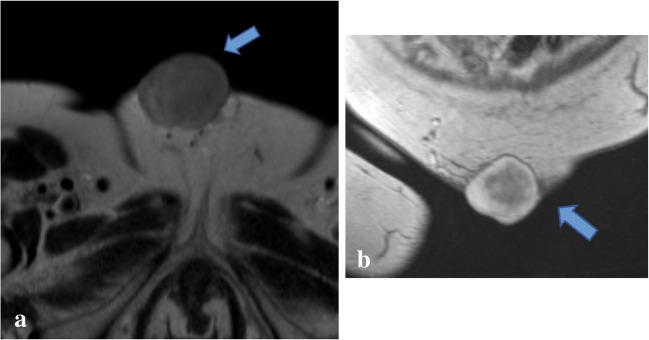

颗粒细胞瘤是一种罕见的源于雪旺细胞的软组织肿瘤。颗粒细胞瘤发生于前腹壁极为罕见,医学文献迄今仅报道了12例良性腹壁颗粒细胞瘤。我们报告一例上腹壁颗粒细胞瘤在最近产后35岁的妇女。根据患者的病史、近期产后表现和影像学表现,软组织肿瘤最初怀疑为硬纤维瘤。因此,在活检和切除后,良性颗粒细胞瘤的最终组织病理学诊断是非常罕见的。在此,我们讨论良性颗粒细胞瘤的独特表现及其诊断检查,包括影像学和组织病理学结果,以强调这种罕见实体在某些腹壁软组织肿块鉴别诊断中的可能性。

Granular cell tumors are uncommon soft tissue neoplasms derived from Schwann cells. It is extremely rare for granular cell tumors to be found in the anterior abdominal wall, with only 12 cases of benign abdominal wall granular cell tumors reported in the medical literature to date. We report a case of an upper abdominal wall granular cell tumor in a recently postpartum 35-year-old woman. Based on the patient's history, recent postpartum presentation, and imaging findings, the soft tissue tumor was initially suspected to be a desmoid tumor. Therefore, following biopsy and resection, the final histopathological diagnosis of benign granular cell tumor was quite unusual. Herein, we discuss a unique presentation of benign granular cell tumor and its diagnostic workup, including imaging and histopathologic findings, to highlight the possibility of this rare entity in the differential diagnosis of certain abdominal wall soft tissue masses.